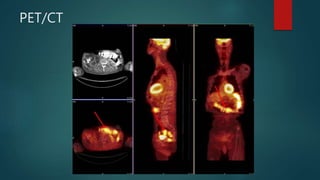

Nuclear Medicine

Pros

 Functional Imaging

 PET/CT is the workhorse for staging in

many neoplastic protocols

 Often provides an adjunct or

alternative to conventional imaging

modalities

 Uses include VQ scan

 Brain death study

 GI bleeding scan

Cons

 Highest radiation dose

 Poor spatial resolution

 Costly

 Slow

 Not always available

PET/CT